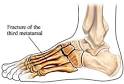

Fractura de los metatarsianos

Fracturas de los metatarsianos: Es la luxación de continuidad de los metatarsianos, los cuales se consideran huesos largos y ocupan gran parte del pie.

Las fracturas de los metatarsianos se pueden clasificar de acuerdo con la localización del trazo de la fractura en:

- Fracturas de la diáfisis, que son las más frecuentes.

- Fracturas de la porción metafisoepifisaria,raras.

- Epifisiólisis, que solo se presentan en los niños y más raramente que las anteriores.